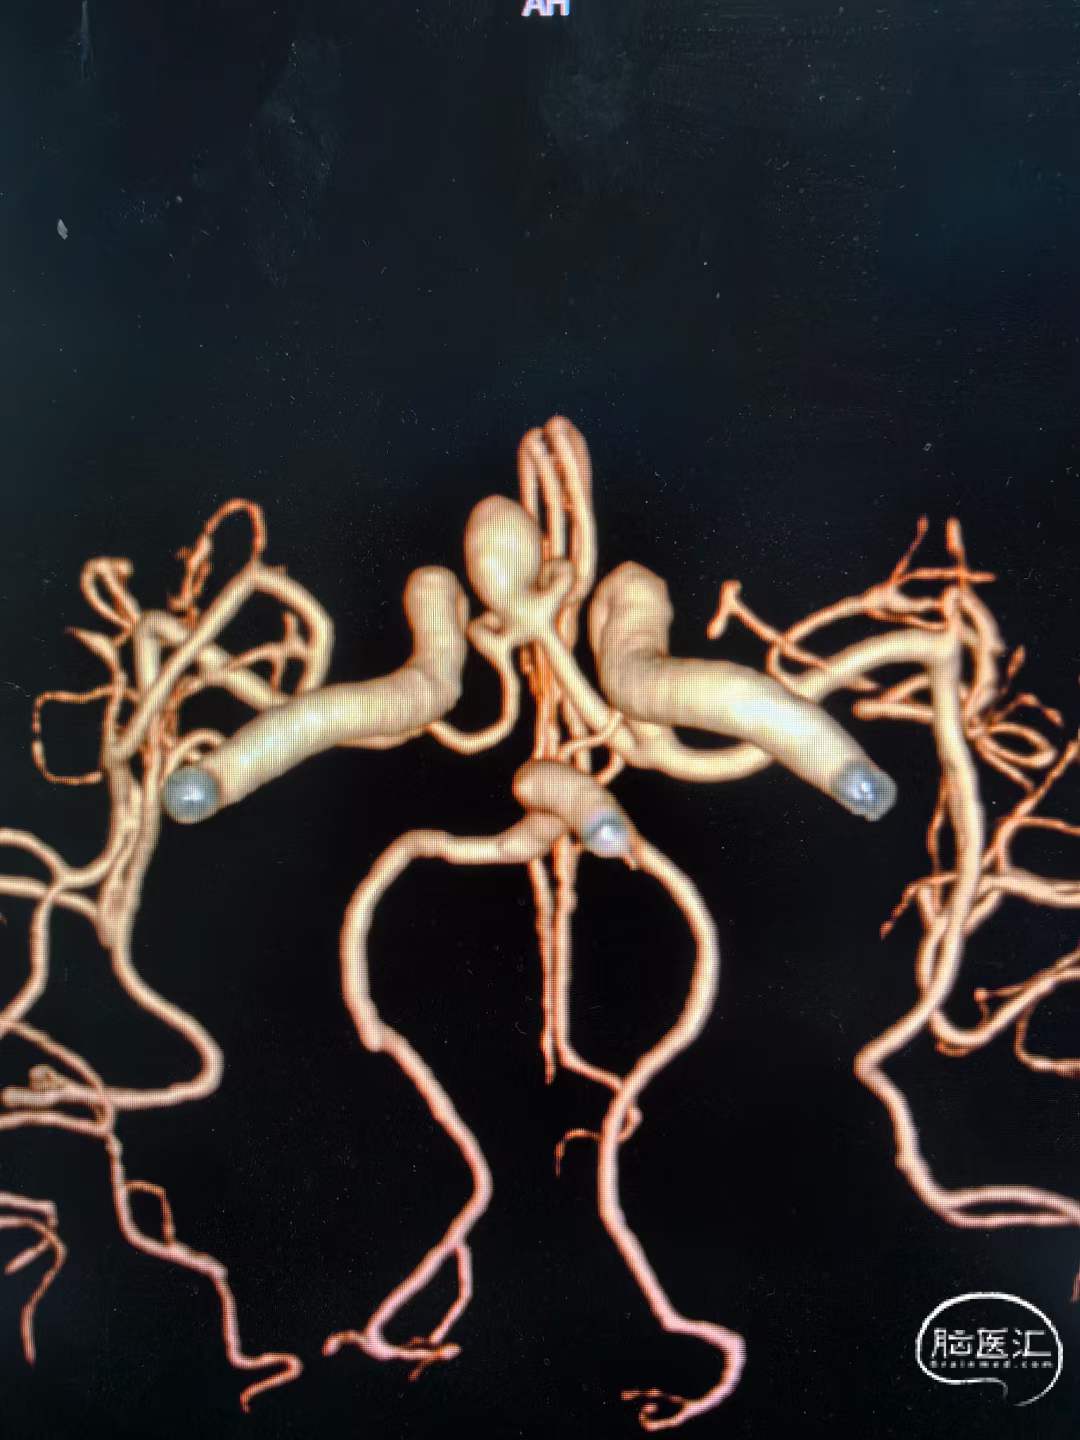

动脉瘤致密栓塞,载瘤动脉血流通畅。

术前术后对比